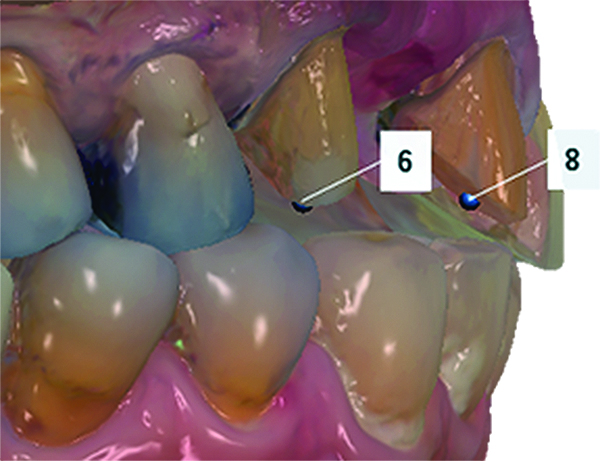

(6.) Examination of the optical impression for undercuts. Note the presence of undercuts (red) labially on the central incisor and mesially on the canine.

Figure 6